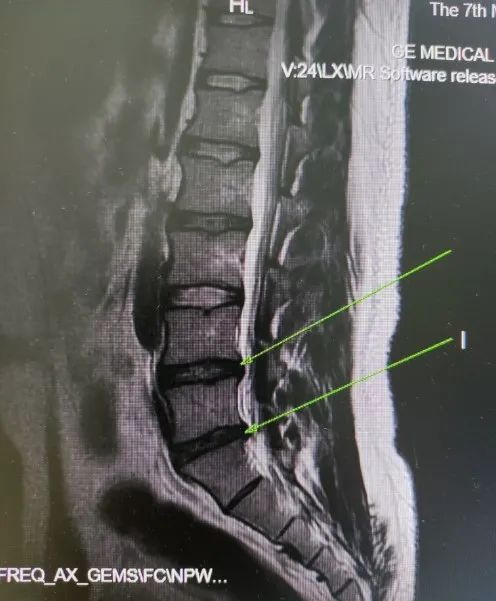

椎间盘病变也需要做磁共振检查

椎间盘突出,在磁共振上显示的比CT更清晰,尤其对神经根和脊髓的压迫也显示比CT要好。

腰椎间盘突出磁共振成像